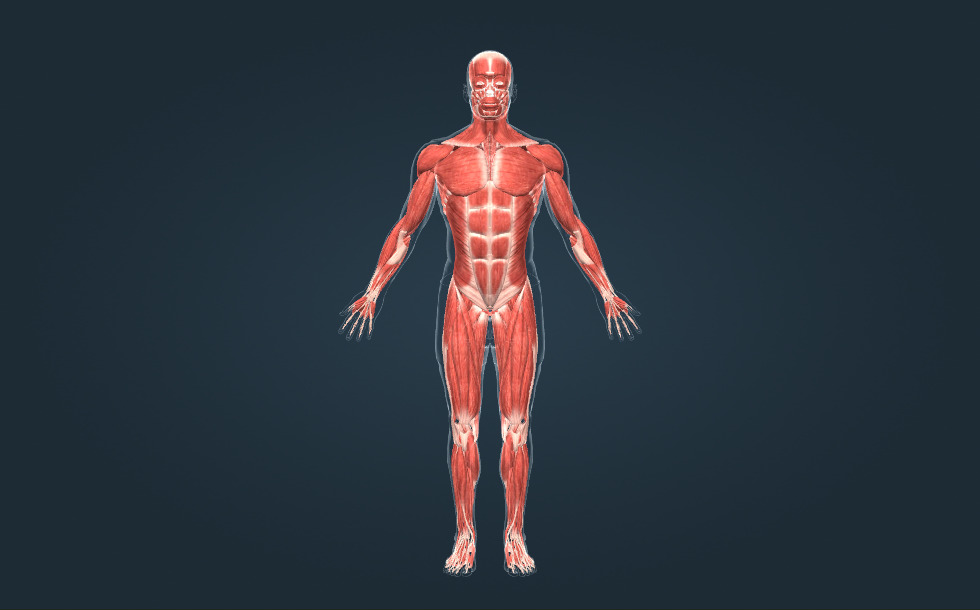

Cơ xương

- các cơ vùng đầu

- các cơ vùng ngực

- các cơ vùng bụng

- các cơ vùng bắp chân

- các cơ vùng cổ

- các cơ vùng cánh tay

- các cơ vùng cẳng tay

- các cơ vùng đùi

- các cơ vùng lưng

Cơ xương là cơ quan vận động chủ động. Cơ thể người có khoảng 350 cơ xương, chiếm khoảng 50% khối lượng cơ thể. Có các cơ dài, cơ ngắn, cơ dẹt và cơ hình vòng. Cơ được gắn vào xương bằng gân.

Cơ xương là cơ quan vận động chủ động. Cơ thể người có khoảng 350 cơ xương, chiếm khoảng 50% khối lượng cơ thể. Có các cơ dài, cơ ngắn, cơ dẹt và cơ hình vòng. Cơ được gắn vào xương bằng gân.